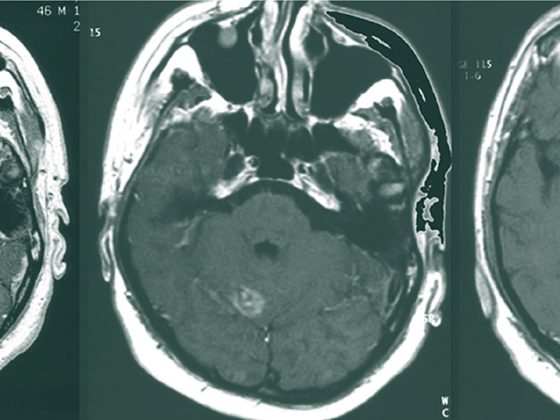

metastase_hirn

• Zerebrale Tumoren

Strahlentherapie von Hirnmetastasen